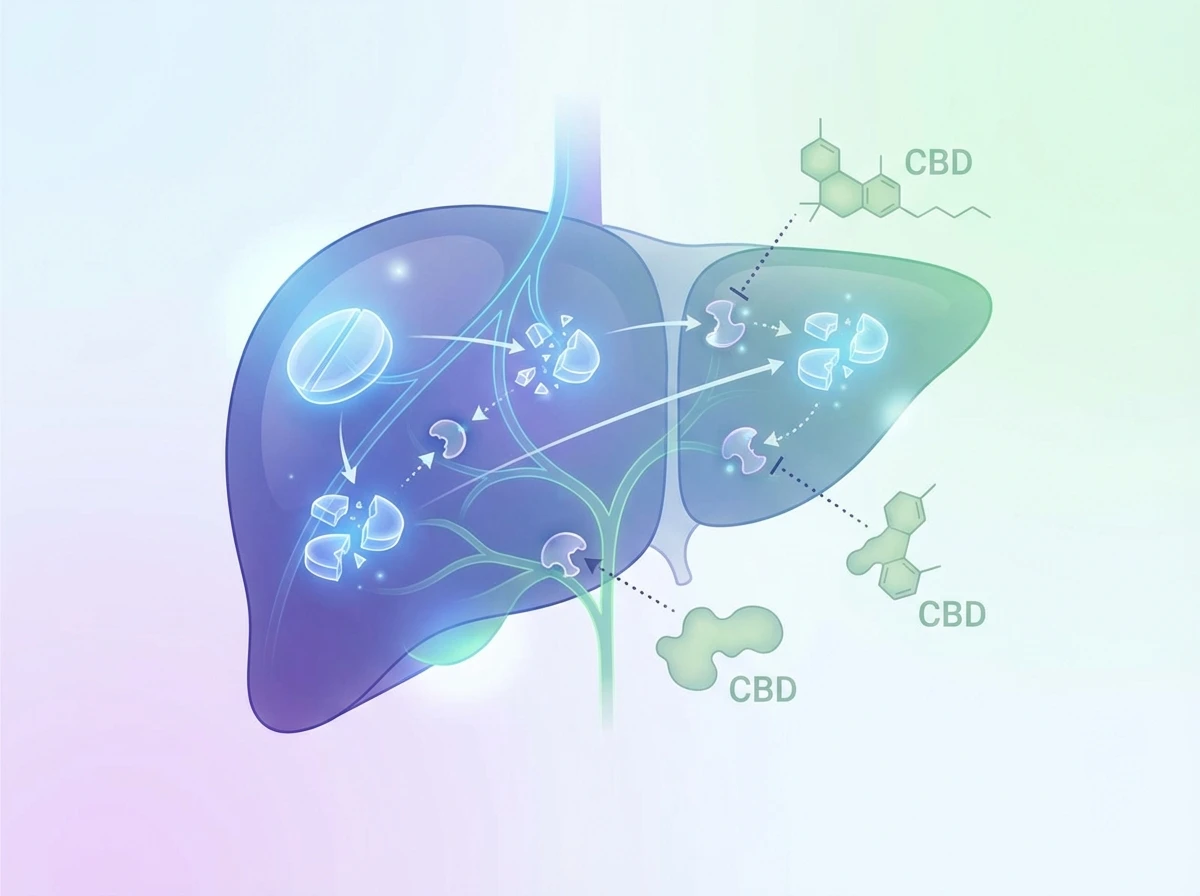

From a practical standpoint, the key detail is that sertraline is processed by your liver, using enzyme systems that also process lots of other medicines and supplements. That is why interactions come up, especially if you add something new on top of a stable routine.

CBD can affect some of the same liver enzyme pathways involved in drug metabolism. In practice, this means CBD could, in some cases, change the amount of sertraline circulating in your system. The goal of this article is to help you reduce risk, spot warning signs, and speak to the right professional before experimenting.

Most potential interactions come back to one theme: metabolism. Your liver uses enzymes (often discussed as CYP enzymes) to break down medicines. CBD can influence some of these enzymes in a dose-dependent way.

Think of it this way: if metabolism slows down, a medicine may hang around longer than expected. If metabolism speeds up, it may clear faster. Either way, it can make your usual dose feel different, even if you have not changed the sertraline itself.